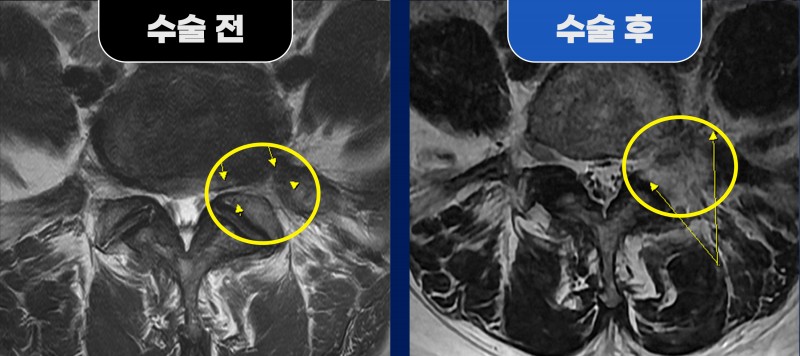

이로 인해 요추 5번 신경이 추간공부터 추간공 외측까지 연속적으로 압박되고 있었습니다.

수술 후 MRI에서는 수술 전 좁아져 있던 추간공부터

추간공 외측까지의 신경 공간이 넓게 확보된 소견이 확인되었습니다.